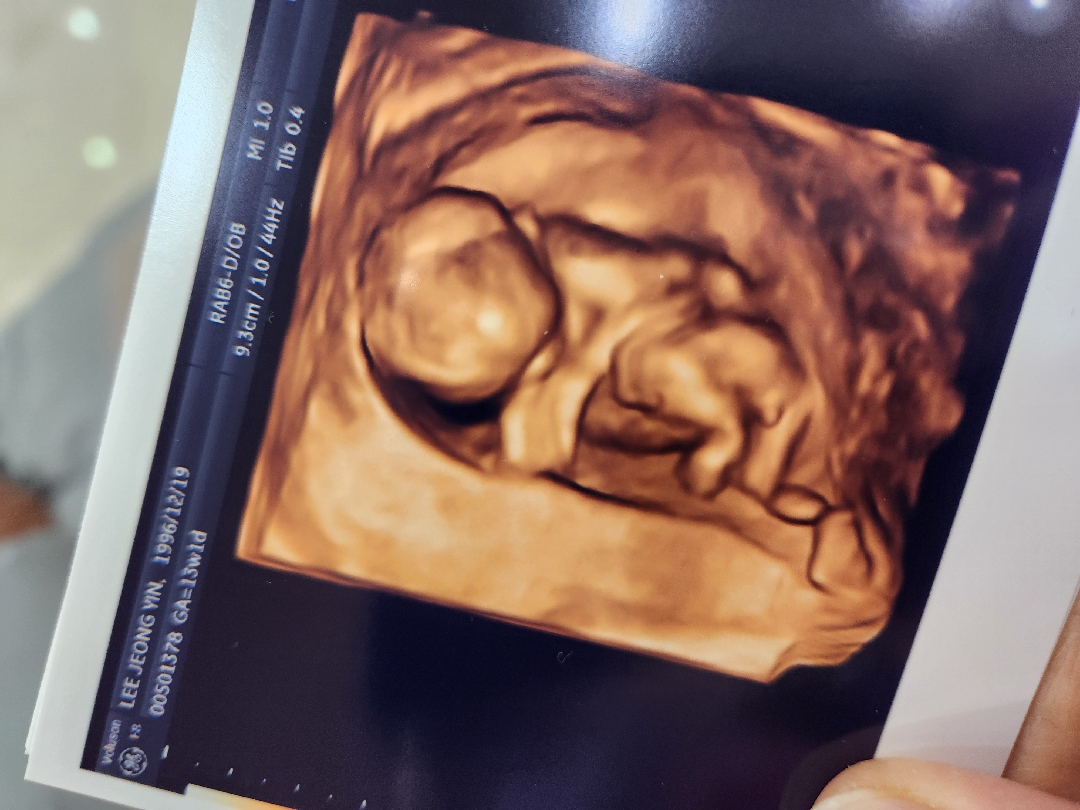

13주인데 이정도 존재감이면...

13주인데 이정도 존재감이면 반전은 없겠죠?.. 혹시 반전있으신분들 있으신가요?😂 아들, 딸 둘다좋지만 막상 아들이라 생각하니 쫌 섭섭해요..ㅠㅠ

초기 입체촘파는 형체만보는거라고 기대하지말라길래 별기대없었는데 생각보다 신기하고 자세히나왔어요ㅎㅎ